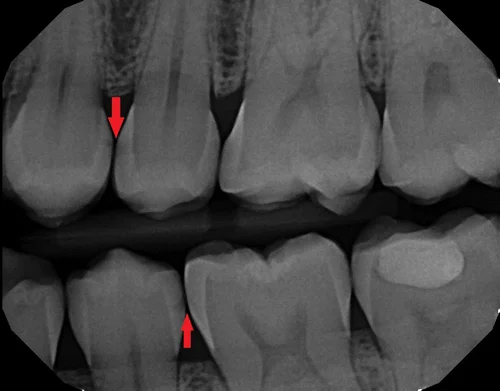

Brushing does not reach every surface of your teeth. If your teeth contact each other, then the bristles cannot clean adequately between your teeth. Flossing works by physically breaking up plaque that accumulates just below the contact of your teeth and in the crevices of your gums between your teeth. It also works by allowing oxygen to reach those areas, which disrupts the anaerobic (oxygen-intolerant) bacteria that cause gum disease and caries.